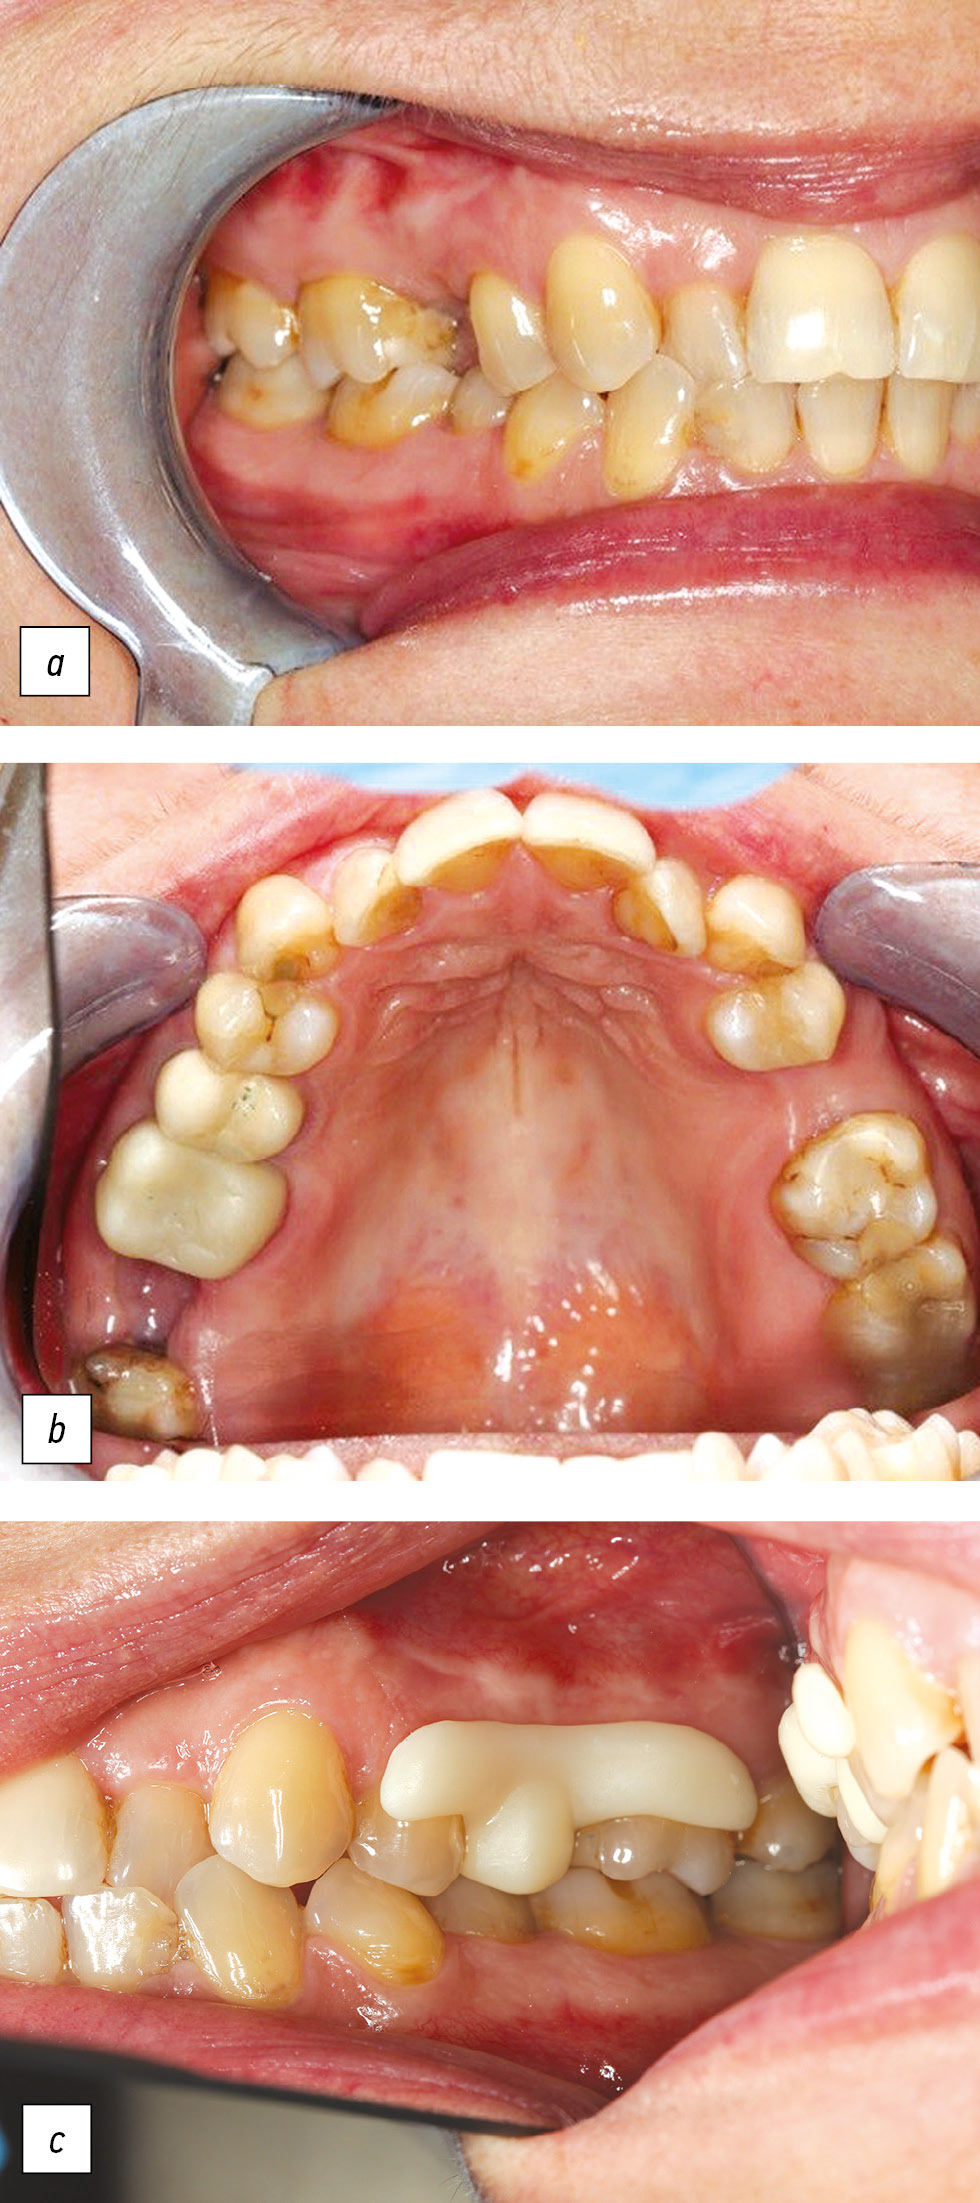

Рис. 2. Пациент Л., 26 лет. Диагноз: частичная потеря зубов вследствие удаления, осложненная смещением зубов.

а, b — ортогнатический прикус; фиссурно-бугорковые взаимоотношения с антагонистами нарушены; зубы, ограничивающие дефект зубного ряда, имеют горизонтальное смещение в сторону отсутствующего зуба 2.5; с — временный съемный протез малой протяженности для лечения горизонтального смещения зубов

Fig. 2. Patient L., 26 years old. Diagnosis: partial loss of teeth due to removal, complicated by displacement of teeth.

a, b — orthognathic bite, teeth that limit the defect of the dentition have a horizontal displacement towards the missing 2.5, the fissure-tubercle relationship with antagonists is broken; с — temporary removable prosthesis of short length for the treatment of horizontal displacement of teeth